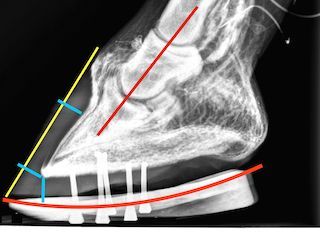

- Spécialiste reconnu de la détection et du traitement de la fourbure, (Coriumite inflammatoire aiguë)